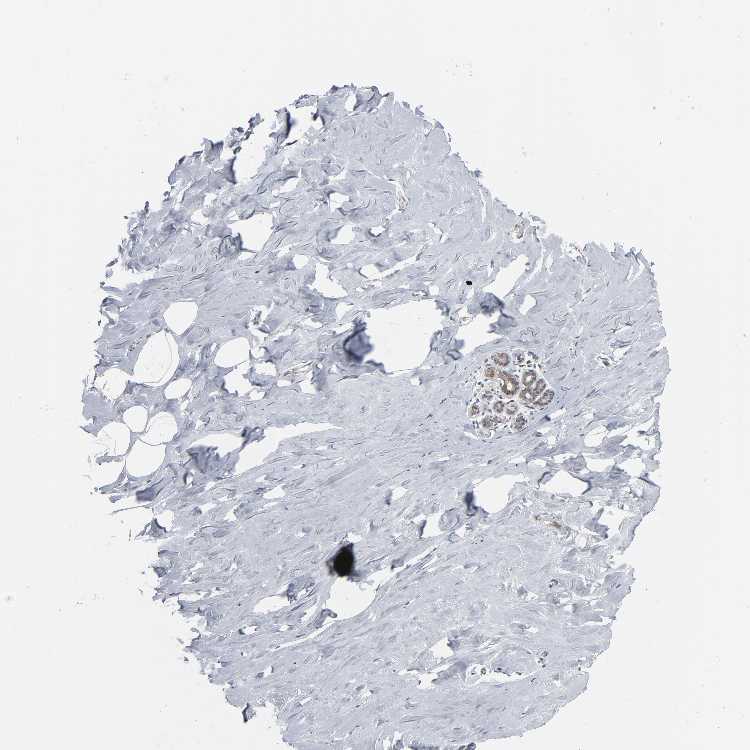

BREAST - Antibody stainingi

Antibody staining in the annotated cell types in the current human tissue is reported as not detected, low, medium, or high, based on conventional immunohistochemistry profiling in selected tissues. This score is based on the combination of the staining intensity and fraction of stained cells.

Each image is clickable and will lead to virtual microscopy that enables deeper exploration of all samples and also displays staining intensity scores, fraction scores and subcellular localization as well as patient and tissue information for each sample.

Antibody HPA004179Antibody HPA007235Antibody HPA008855Antibody CAB000036Antibody CAB001986Antibody CAB080102Antibody CAB080103

Adipocytes Not detectedNot detectedNot detectedNot detectedNot detectedNot detected-

Glandular cells MediumLowHighMediumMediumNot detectedMedium

Myoepithelial cells LowNot detectedHighNot detectedNot detectedNot detectedNot detected